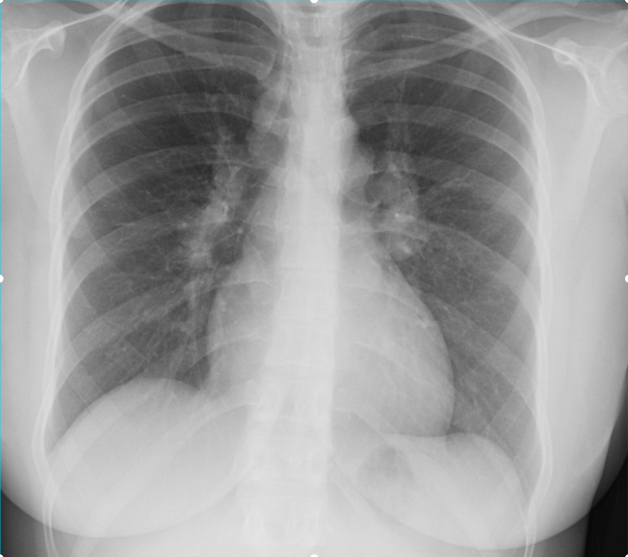

A 26-year-old man comes to the physician because of a 1-week history of left-sided chest pain. The pain is worse when he takes deep breaths. Over the past 6 weeks, he had been training daily for an upcoming hockey tournament. He does not smoke cigarettes or drink alcohol but has used cocaine once. His temperature is 37.1°C (98.7°F), pulse is 75/min, and blood pressure is 128/85 mm Hg. Physical examination shows tenderness to palpation of the left chest. An x-ray of the chest is shown. Which of the following is the most appropriate initial pharmacotherapy?